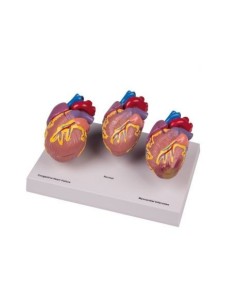

Dal cranio in 22 parti con incastri magnetici ai modelli di colonna vertebrale, da quelli di articolazioni a quelli di cuore, ogni pezzo della nostra collezione è progettato per un’immersione totale nello studio dell’anatomia umana. I nostri modelli, realizzati tramite scansioni di ossa vere, garantiscono un’esperienza tattile autentica e una fedeltà di peso quasi identica agli originali.

Essenziali per studenti e professionisti, i nostri modelli anatomici sono strumenti didattici che permettono di osservare le strutture anatomiche con precisione, eliminando la necessità di dissezioni o studi invasivi. Sono inoltre utili per spiegare ai pazienti le patologie, rendendo la comunicazione più efficace e risparmiando tempo prezioso.